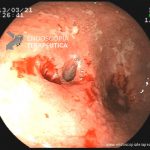

- Doença de Crohn em atividade

- Doença de Crohn em atividade leve